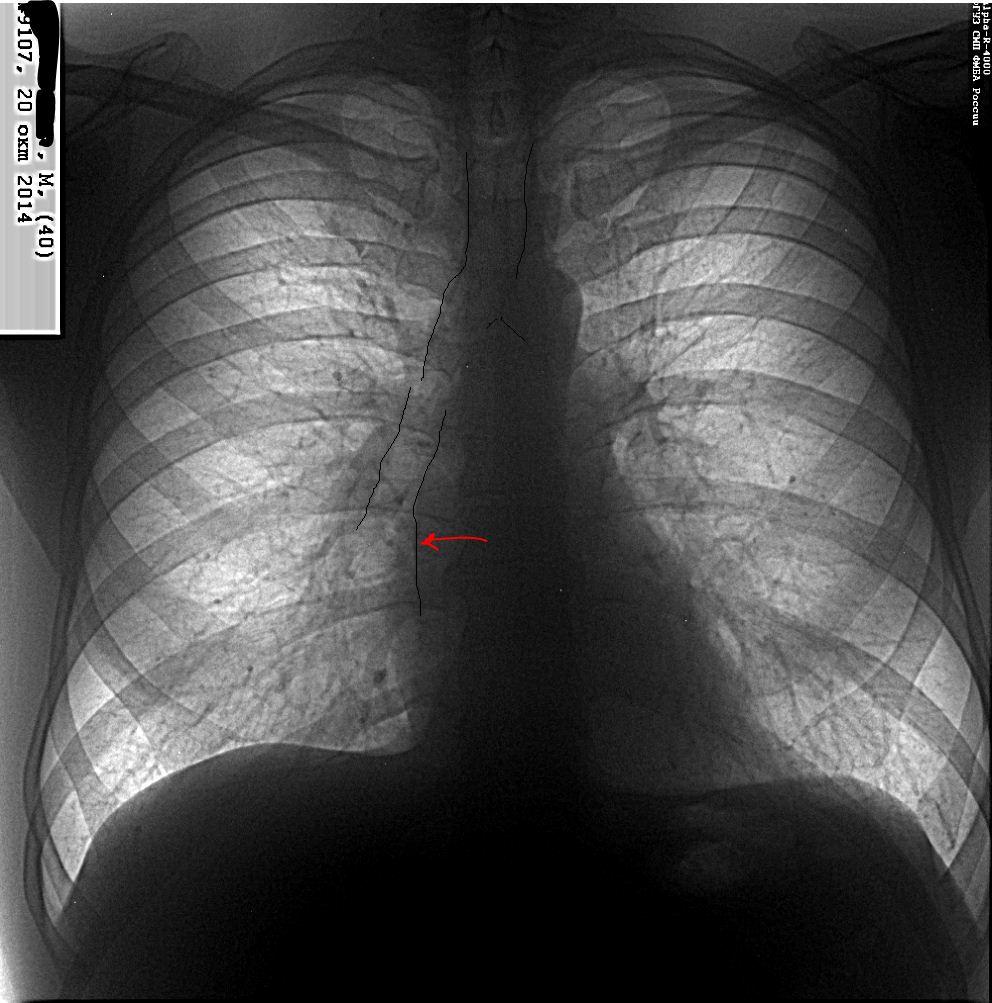

Медосмотр. Без жалоб. Подскажите, чем это может быть анатомически. Для обызвествления аорты в 40 лет рано. Плотнее и медиальнее правого контура предсердия. Может это "дно" т.н. атрио-пульмональной борозды, обусловленной захождением (огибанием) легочной тканью предсердия?

Возможно нисходящая часть аорты. Проведите рентгеноскопиюю.

Я тоже думаю, что нисходящая аорта

Нил, аорта НЕ МОЖЕТ в норме быть краеобразующей 1-й дуги справа в прямой проекции - так меня учили, тогда еще УЗИ и КТ не было))))

О, художники! Немного фантазии+художества=...Талантливые во всех отношениях рентгенологи! Но сейчас немного расстрою. Аорта здесь не при делах. Это контур ,так сказать ,края ложа атрио-пульмональной борозды, образованной медиастинальный плеврой( выходит на контур при "завороте" и обычно наблюдается только при цифровых снимках). Не знаю, понятно ли выразилась, но -не аорта.И не медиальный край бронха( для алкса), он-немного латеральней вправо( то есть влево от нас, средостения) уходит.

А я бы согласилась с NIL в том, что это тень восходящей аорты. Потому что атрио-пульмональная борозда (если я правильно понимаю, это azygo-esophageal recess) в норме здесь проходить не должна, она должна быть значительно левее. На рисунке я показала ее синим цветом, это ее нормальное положение, если же она смещена, то это патология, которая может быть вызвана патологией пищевода, расширением левого предсердия или образованиями средостения.

Мне думается, что для восходящей аорты слишком низко и прямолинейно.